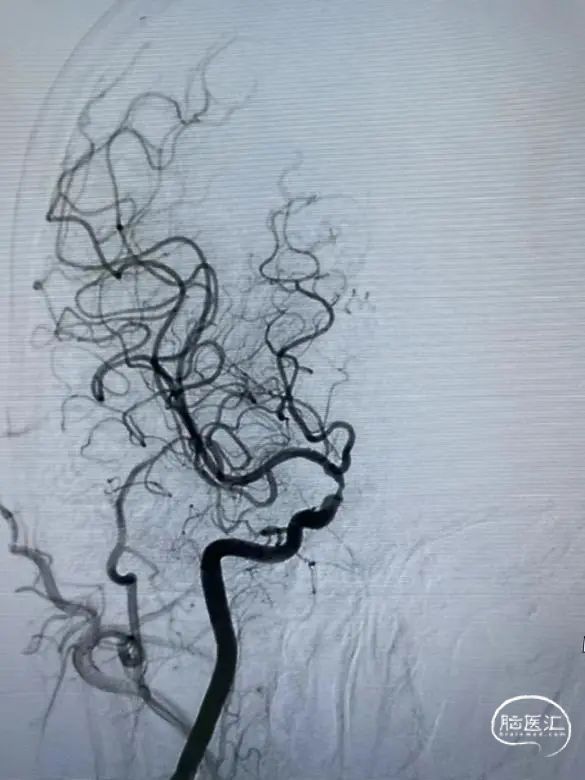

半年后复查造影支架内再狭窄。

2

加奇SacSpeed®2.0×15mm球囊预扩张后2×10mm药涂球囊扩张。

3

狭窄明显改善。

对于支架内再狭窄患者,药物球囊扩张治疗可抑制内膜增生,降低再狭窄率